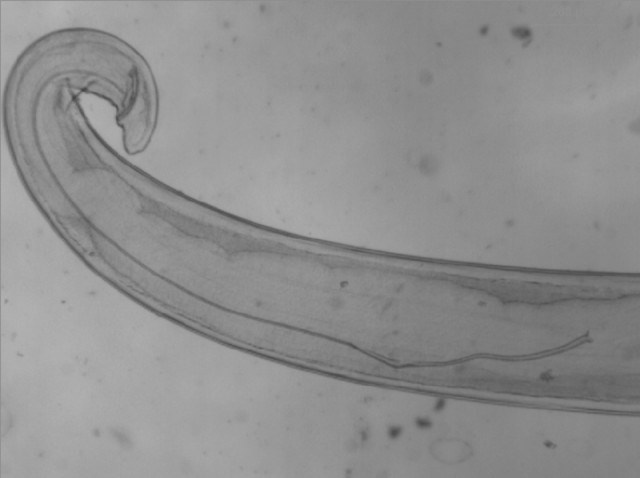

Loài giun tròn Thelazia gây bệnh ở mắt, ký sinh ở một số động vật có vú, được truyền qua trung gian ruồi Dipteran. Thelazia được phát hiện năm 1910, thường thấy ở vùng Viễn Đông. |

![]() |